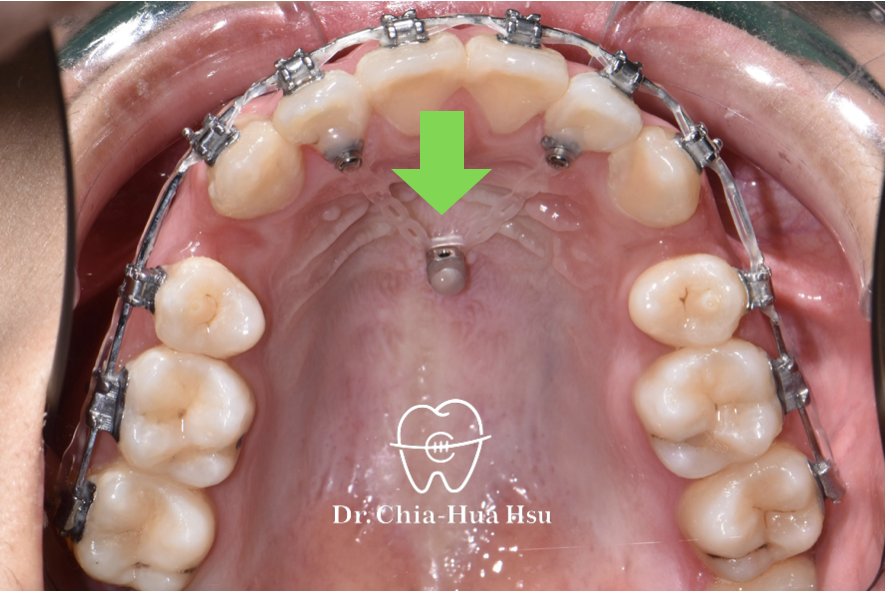

- 外觀與尺寸:矯正骨釘非常小,形狀類似迷你螺絲,一般長度約 6–12 毫米、直徑 1.5–2 毫米。

- 骨釘的作用:矯正骨釘就像在骨頭裡多加了一個「超穩固的固定點」,醫師能利用它施加更精準、穩定的力量,幫助牙齒移動到正確位置,而不會因互相牽制而偏移。

- 當牙齒的移動方向或距離較困難且複雜的時候,矯正骨釘就派上用場。其主要用途包括:

- 壓低過高的前牙或後牙(如深咬、開咬、過度萌發的牙齒)

- 往後拉動整排齒列(遠心移動)

- 在牙齒缺損區缺乏支點時提供穩定施力